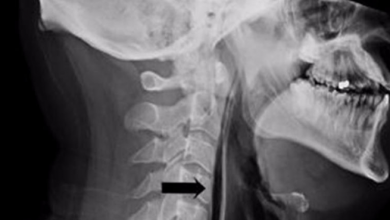

رجل بريطاني يصاب بكسر في الرقبة بسبب كتم عطسته